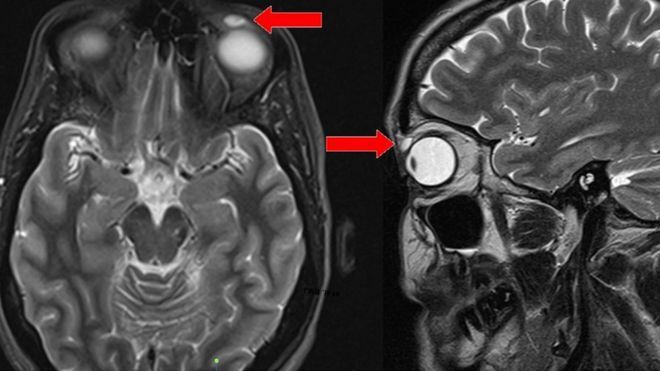

I ricercatori dell’ospedale di Ninewells hanno effettuato una risonanza magnetica dopo che la donna è stata indirizzata dal Dipartimento di oftalmologia dal suo medico di famiglia.

Le immagini hanno rivelato una cisti a forma di ovoide lunga circa 8 mm ma non c’era alcuna evidenza di qualcosa al suo interno.

Quando i chirurghi hanno rimosso il nodulo, la cisti si è rotta e ha rivelato il contenuto.